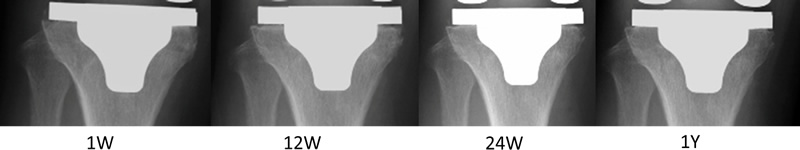

内側領域の骨密度は、PA群において術後2週と比し、1.5年にかけて有意に漸減していった。RE群では、内側領域において低下することなく維持されていた。2機種間の比較では、術後1年および1.5年時には、PA群はRE群に比して有意に骨密度が低下していた(図5a)。外側領域では、PA群では経過中増減はなかったのに対し、RE群では術後6ヶ月で有意に上昇し、その後維持されていた(図5b)。キール先端領域では、PA群もRE群においても骨密度は術後有意な増減はなかった(図5c)。X線学的検討では、骨密度低下を来す内側領域において術後早期に0.5~1mm程度の隙間が出来る。そしてそれは、2年までに全例骨侵入が起こり埋まっていった(図6)4)

cv_hachiya_01_06_01.jpg

図6a. 82歳女性 左TKA

両症例とも1~2mmのRadiolucent lineが出現したが、徐々に縮小し埋まる。